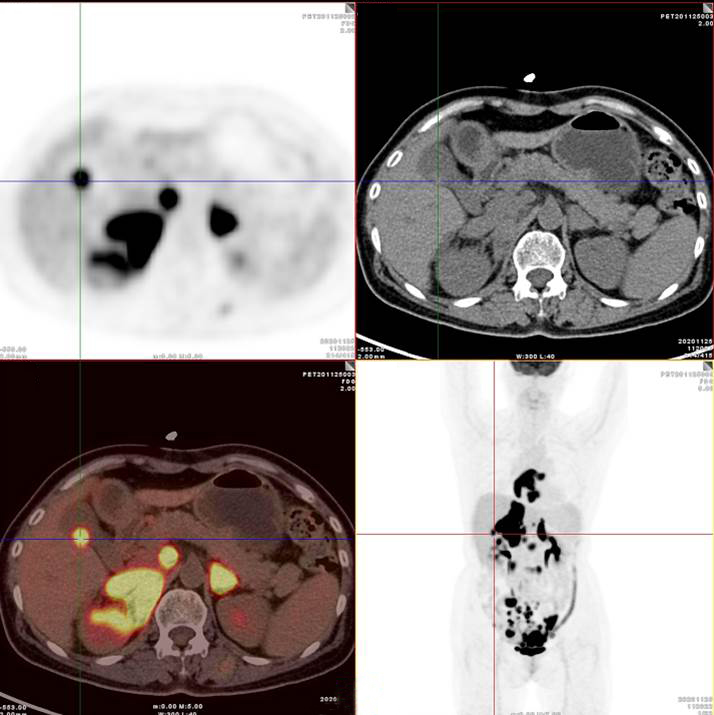

雙側(cè)腎上腺病灶、腹膜后淋巴結(jié)放射性攝取明顯增高

膽囊及雙腎上腺病灶、腹膜后淋巴結(jié)放射性攝取明顯增高

胃、雙腎上腺病灶、腹膜后淋巴結(jié)放射性攝取明顯增高